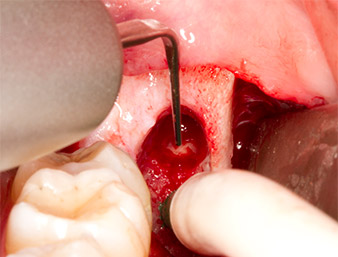

After block and local anaesthesia, the operating site was opened up and the soft tissue exposed for buccal retromolar access (Fig. 3).

The tissue above the root remnant was not completely ossified and consisted for the most part of granulation tissue modified by inflammation (Fig. 4).